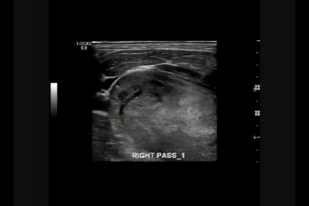

• Обложка: 1.4 Ультразвуковое исследование гортани при обследовании парализованной правой истинной  голосовой связки